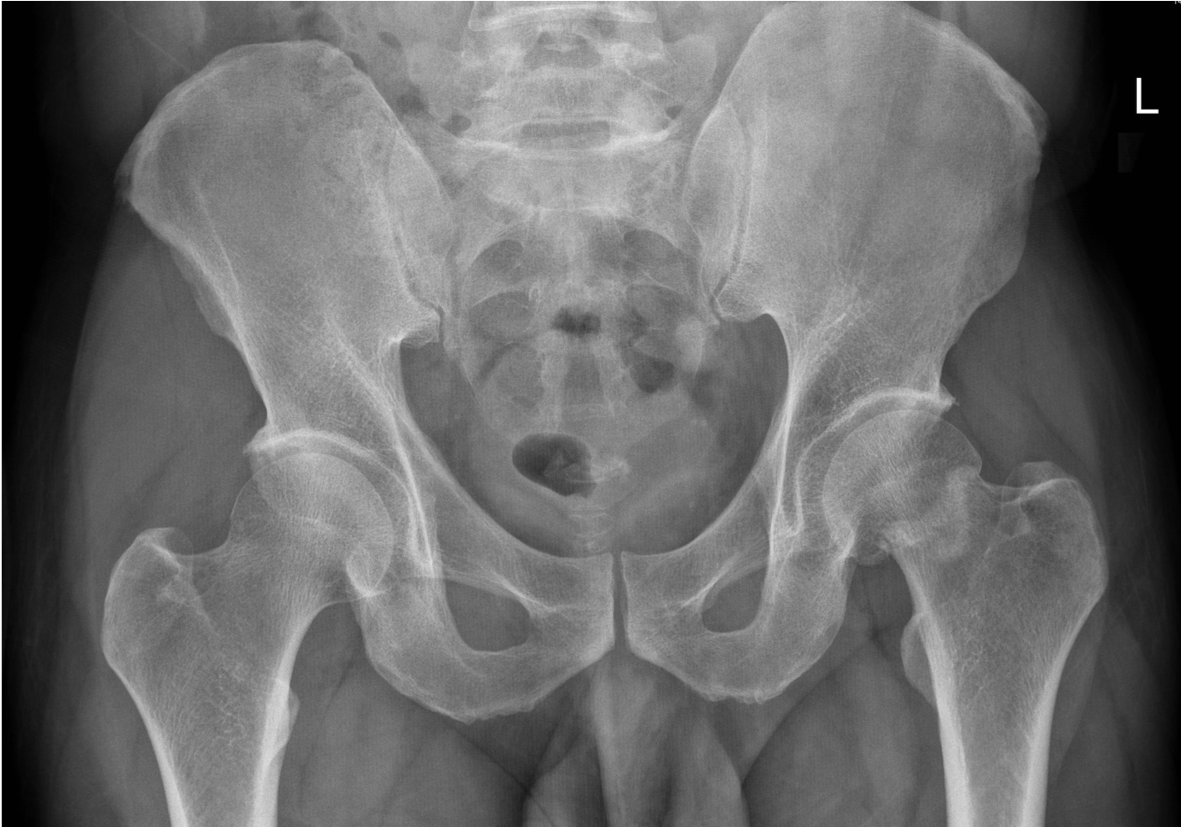

A 70 year old woman presented to her GP with a long history of pain in her left knee that was becoming worse and limiting her movement.

On examination the patient had a good range of movement, but there was some discomfort in her left knee on movement and crepitus (crunchy noise and feeling when moving joint).

This 75 year old woman presented with difficulty walking and knee pain. How would you describe these X-rays?